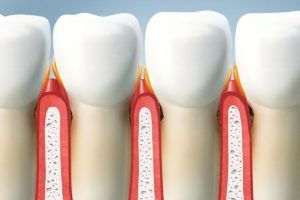

Qué dice el color de las encías sobre tu salud bucodental

El color de las encías puede darnos pistas sobre cómo se encuentra nuestra salud oral y general. Descubre qué significa cada uno y evita problemas graves. La salud bucodental está estrechamente relacionada